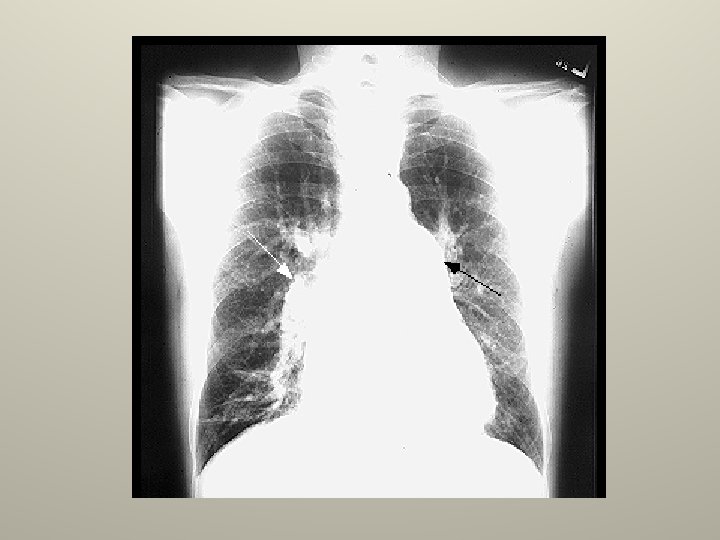

Pequeño Neumotorax www. reeme. arizona. edu

Gran Neumotorax www. reeme. arizona. edu